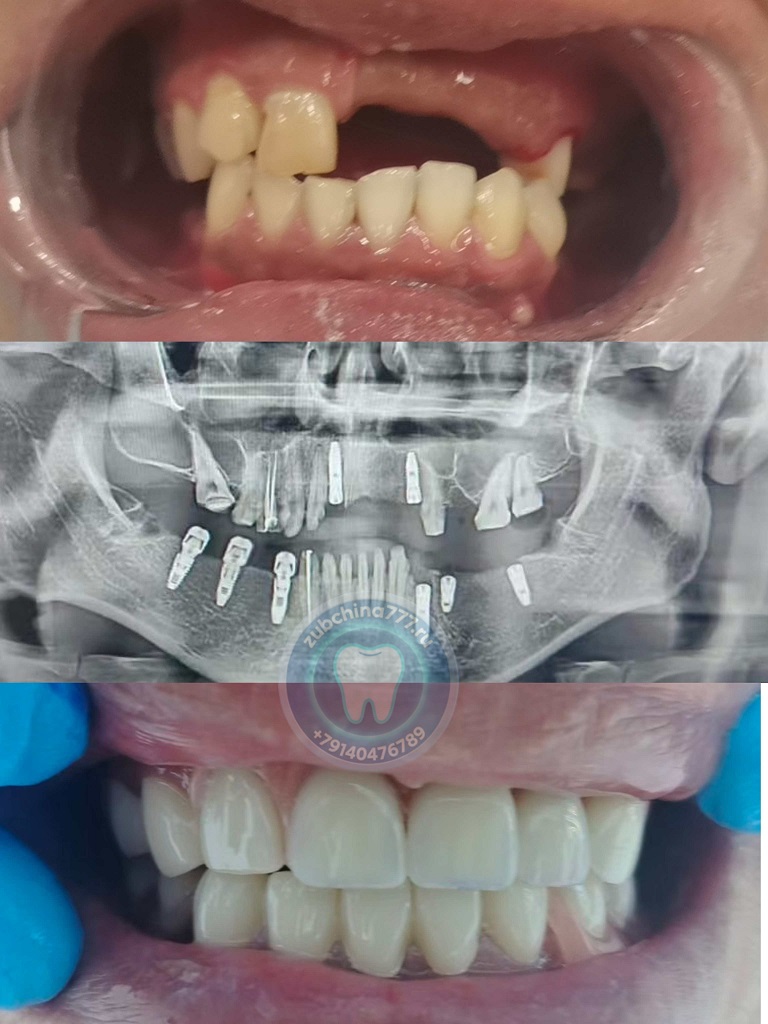

Фотографии пациентов ДО и ПОСЛЕ лечения и протезирования зубов в Хэйхэ